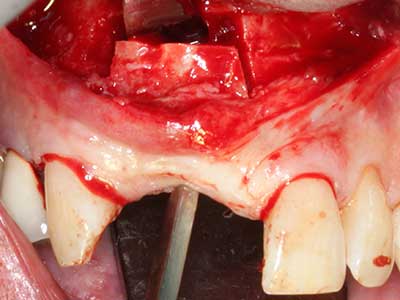

Piezo surgery has additional advantages when harvesting bone blocks. In addition to the high precision with osteotomy described above, the use of the thin saw tips specifically minimizes loss of material. Greater loss of material during harvesting can be expected with the thicker instrument tips, particularly when using Lindemann drills (Lakshmiganthan, Gokulanathan et al. 2012). The basal separation, which is necessary particularly for retromolar block transplants, is simplified by specially designed rectangular saws, with the result that piezo surgery is viewed as a precise, simple and safe procedure for harvesting retromolar bone blocks (Happe 2007) (Fig. 1-12).